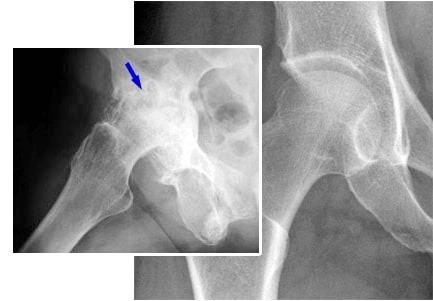

Liječenje zglobova lakta. Žena. 31 godina. Trajanje liječenja: 2 mjeseca. Hrskvica se potpuno oporavila: